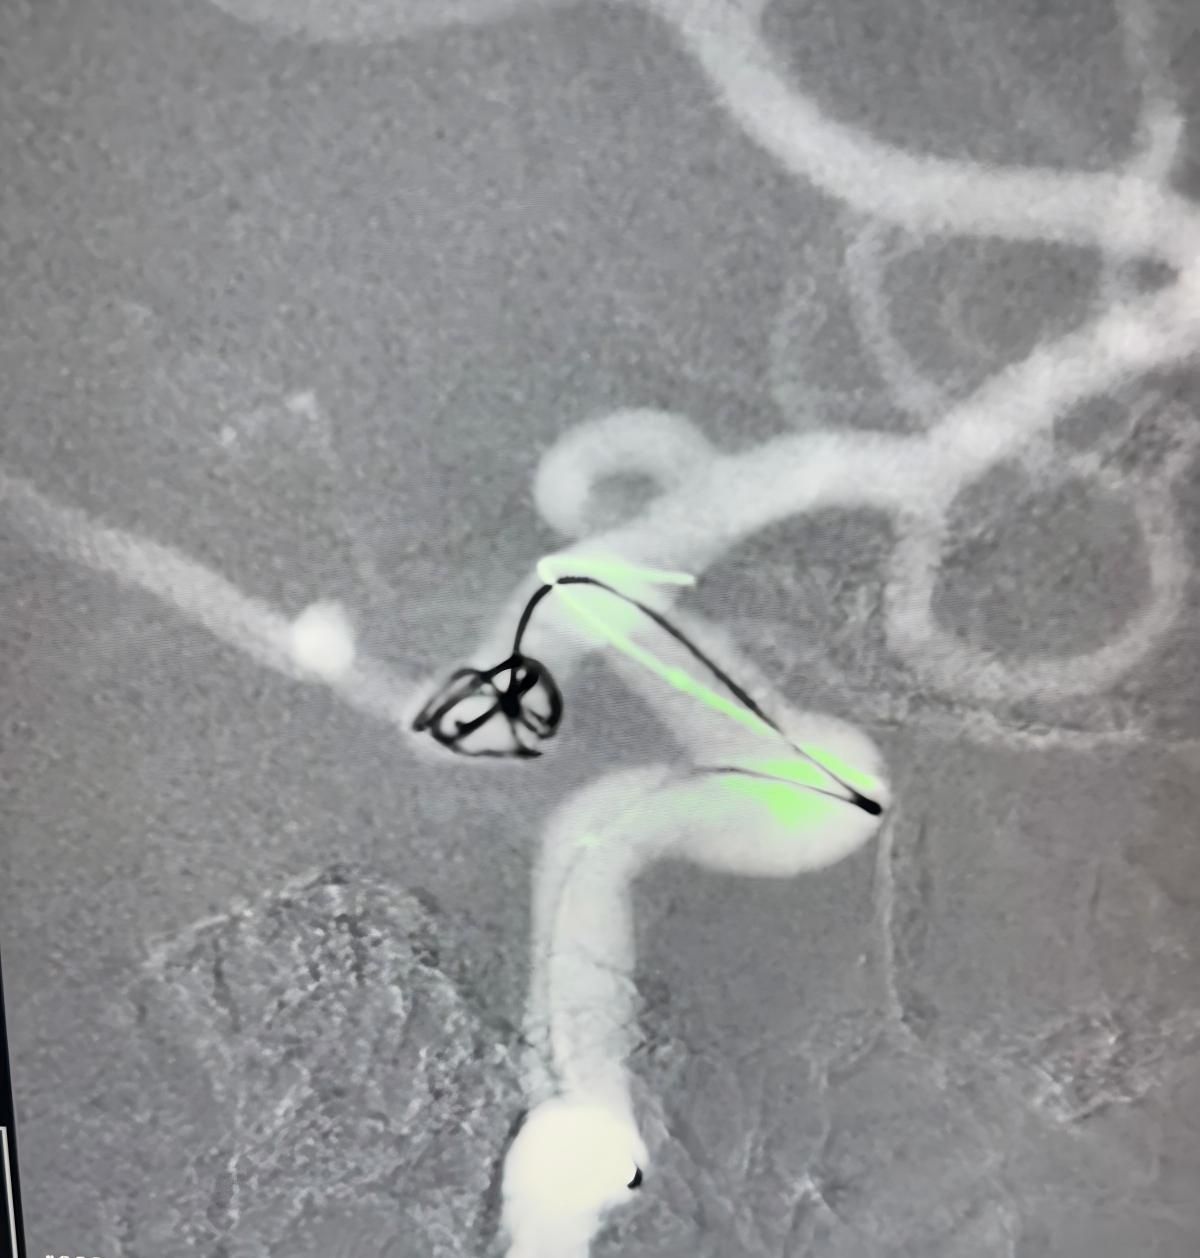

O tratamento utilizou a Nuva®Desvio de fluxo (TJED-D 5.0-14), Perdenser®Bobina 3D, e Frepass®Microcateter (TJMC18 Plus) para aneurisma da artéria comunicante posterior.

O Dr. Mutis destacou a excelente visibilidade do dispositivo e observou que a recuperação foi suave. Ele expressou grande satisfação com o resultado final.